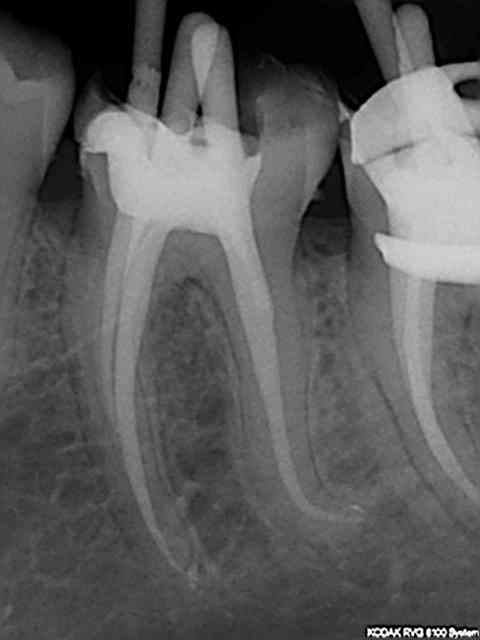

90 mn 2 molar endo + extrac 38. Un peu lent du à la difficulté à anesthésier (30 mn). les crochets apicaux traités comme si ils n'existaient pas avec le r25.

les 6 canaux avec le même r25. Attention toutefois je m'y suis repris à plusieurs reprises pour envoyer le s1 à l'apex (alternance r25 s1) et une bonne ouverture des entrées au largo ainsi qu'une très large cavité d'accès. Je n'ai à ce jour jamais cassé de r25, mais jamais essayé avec les plots en plastique .)

cela n'était pas des petites racines lt 24-25 mm. Big up à la digue qui m'a apporté un très gros confort de travail et m'a fait gagner du temps. Il n'y a que les imbéciles qui ne changent pas d'avis.

Maintenant pour peaufiner l'action du sx avant le passage du s1 un petit coup de r25 pour progresser d'avantage n'est pas interdit (pas de fausse route avec pour l'instant)c'est ce que j'ai fait sur ces 2 molaires ou la radio préop laissait présager un peu de sport. )))

connais pas. Mais une de plus 30 mn, résultat reproductible à un train de sénateur, po pom, po pom.) Radio cone en place facultative mais bon des fois je coupe le bout du cone..